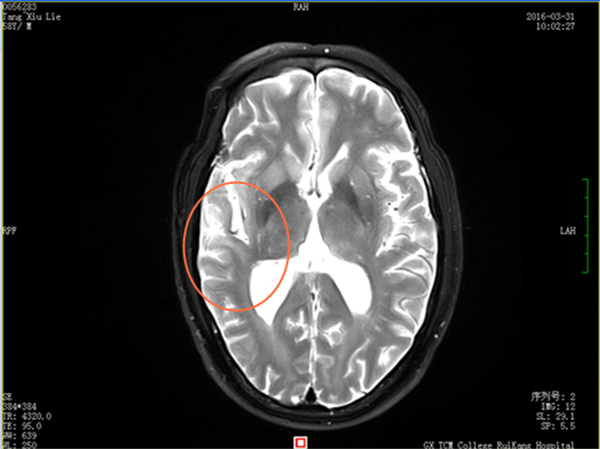

今年58岁唐先生,因多年前误食“米猪肉”,在四年前被确诊为“脑囊虫病”、“症状性癫痫”。行驱虫、抗癫痫治疗后病情好转,之后癫痫没有再发。但在2016年3月初,在无明显诱因的情况下,唐先生出现头晕,伴四肢乏力,为求进一步诊治来到瑞康医院脑病科住院治疗。经检查,在唐先生的MRI增强检查中发现颅内有炎性亮点,进一步血清检查证实为脑囊虫病,经针对病情治疗后得到控制,病灶逐渐消失,症状也得到了明显的改善。

治疗后